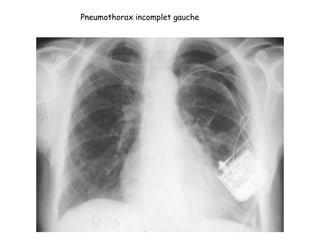

Pneumothorax incomplet gauche